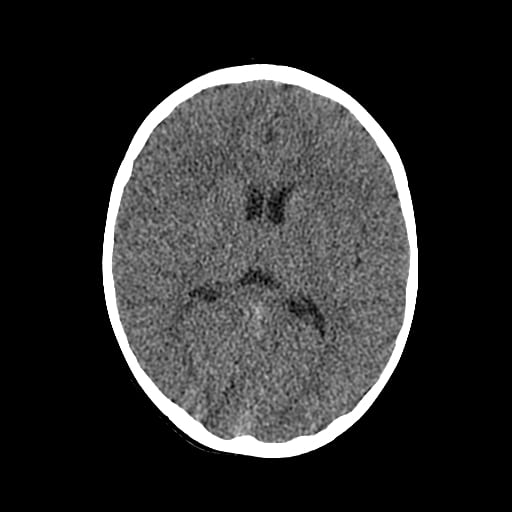

Age: 1

Sex: Male

Indication: Fall